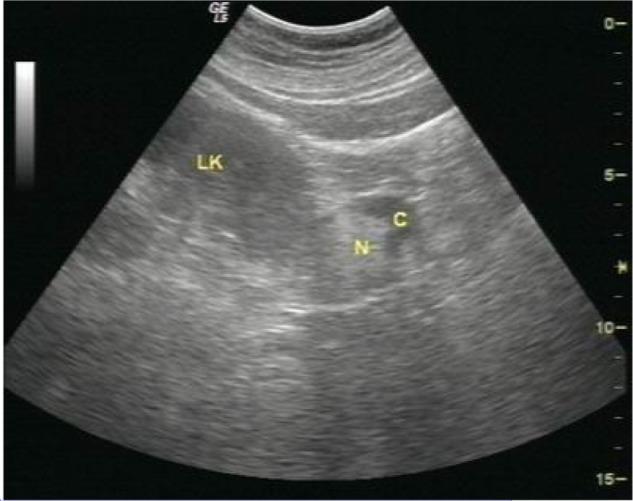

Metanephric adenoma (MA) is a rare epithelial tumor of the kidney with a characteristic histology. To date, the imaging features of the tumor have not been clearly described. Until now, MA was considered to be benign, but the majority of MA cases underwent nephrectomy. Here, we report a case of MA confirmed by surgical pathology, and we will analyze the ultrasound and computed tomography findings. The radiological features of MA are presented along with a brief review of the pertinent literature to deepen the understanding of MA's imaging features.

后肾腺瘤(MA)是一种罕见的具有特征性组织学表现的肾脏上皮性肿瘤。迄今为止,该肿瘤的影像学特征尚未得到明确描述。在此之前,MA被认为是良性的,但大多数MA病例都接受了肾切除术。在此,我们报告一例经手术病理证实的MA病例,并分析其超声和计算机断层扫描结果。本文展示了MA的影像学特征,并对相关文献进行简要回顾,以加深对MA影像学特征的理解。